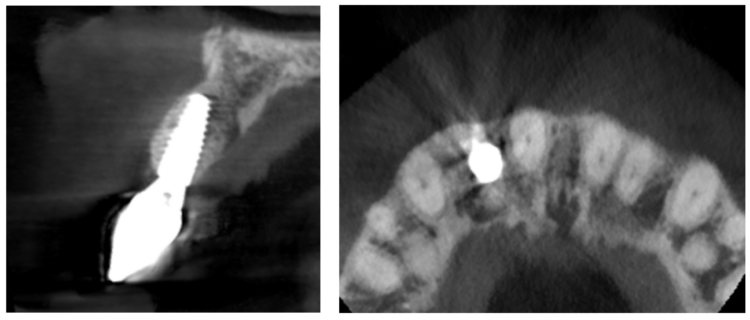

Healing was uneventful and following a seven-month maturation period, a CBCT scan confirmed the presence of the MinerOss®/autogenous bone graft and a favourable volume of bone. However, it was noted that the soft tissues covering the bone graft were thin with an absence of interdental papillae. It was determined that a connective tissue graft would be required as part of the next surgical procedure to improve the soft tissue volume and lead to the creation of papillae during the prosthetic stages.

Healing was uneventful and following a seven-month maturation period, a CBCT scan confirmed the presence of the MinerOss/autogenous bone graft and a favourable volume of bone.